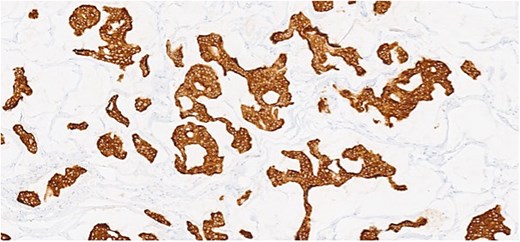

Herein, we present a 75-year-old man who, having been referred to our service with an inguinal hernia, raised concern about a palpable mass present in his right axilla. The main differential on initial examination was that of a simple epidermoid cyst, and consent was obtained for its removal during his elective hernia repair. Subsequent histology however, revealed a well differentiated MAC. There was extensive involvement of the deep and superficial reticular dermis (Figs 1and 2). Lymphovascular invasion was present. Sweat glands were focally involved by the carcinoma. The differential diagnosis included PCMC and metastasis from other primary sites of MAC such as breast, lung and gastrointestinal. Immunohistochemical profiling was performed on the specimen. CK 7, HER2 (4B5, 3+), GATA3 (strong, diffuse), and P16 (focal, weak) were positive (Figs 3–6). SOX10, CK 20, CDX2, TTF-1, p40, ER, and PR were negative which supported the diagnosis of MAC with either breast or PCMC origin based particularly on GATA3 expression.

(a, b) Section of skin showing dermal lesion composed of nests of tumor cells floating in pools of extracellular mucin.

Section showing tumor cells with low to intermediate nuclear grade floating in pools of extracellular mucin separated by fibrous septa.